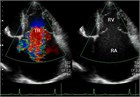

1. TRのほとんどが二次性なので、原疾患の治療を優先するのが基本である。

1. 弁に異常がなく、弁輪拡大のみの場合は人工弁輪を使った弁輪形成術が最も一般的である。弁狭窄や感染性心内膜炎の合併があれば、弁置換が必要である。弁輪石灰化が強く、弁置換も弁輪縫縮も困難である場合は弁尖同士を縫い付ける(クリップをかける)方法が有効である。